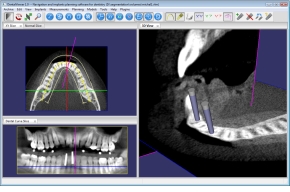

Download > DentalViewer

DentalViewer Releases

Navigation and implants planning software for dentistry. | Download |